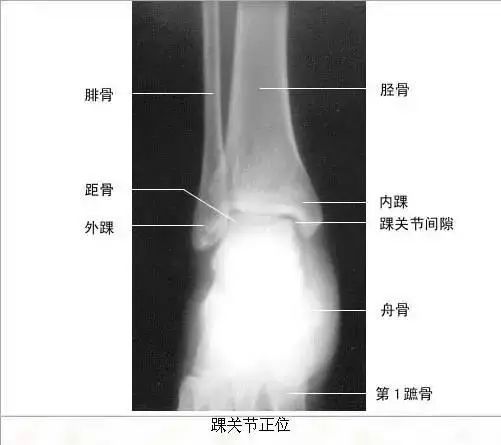

【实用干货】人体体表标志定位与解剖(含人体解剖图)